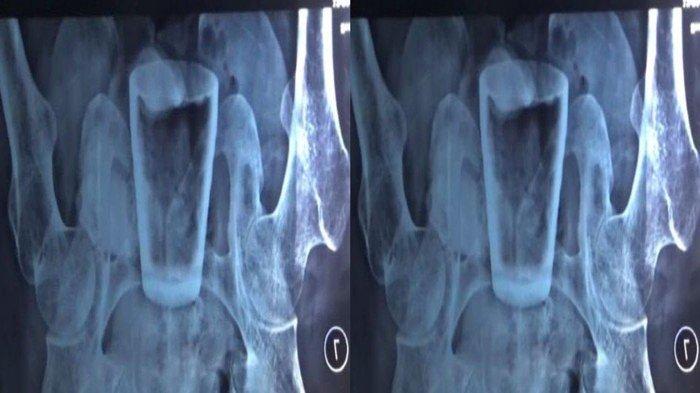

Pasien yang mengeluh nyeri di perut itu diperiksa dan menjalani rontgen.

“Kami foto rontgen dulu, ternyata ditemukan bentukan berupa gelas,” kata Doddy.

Hasil foto rotgen tubuh warga Jember yang berisi gelas pecah di bagian atas (Kompas.com/ Dok Pribadi Lasiadi)

Berdasarkan foto rontgen itu, terlihat gelas kaca di dalam tubuh Lasiadi.